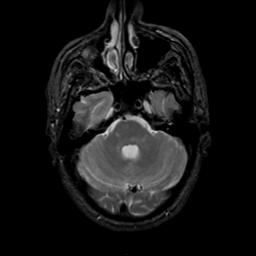

MR Study #22, December 1, 1991 -- Slice #13

[Home][Help][Clinical][Tour 1][Tour 2] Slice 13